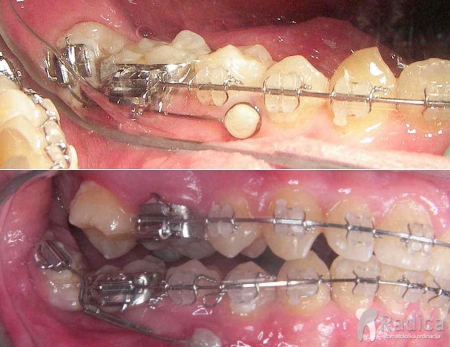

Ortodontski mikroimplantati

To su mali titanski implantati dužine 6, 8 ili 10 mm koji nam pomažu da pomaknemo određene zube a da ne opterećujemo ostale zube ili da zamjene zube koji nedostaju. Postavlju se između korijenova zuba. Mikroimplantati su privremeni i vade se čim više ne trebaju. Stavlja ih ortodont u lokalnoj anesteziji.

Pomoću mikroimplantata pomičemo prednje zube natrag, jer ne možemo opteretiti stražnje zube (pomakli bi se naprijed u ekstrakcijske prostore).

Uspravljanje nagnutog umnjaka pomoću mikroimplantata da zauzme mjesto prethodno izvađenog drugog molara:

Pojačananje sidrišnog zuba pomoću mikroimplantata: